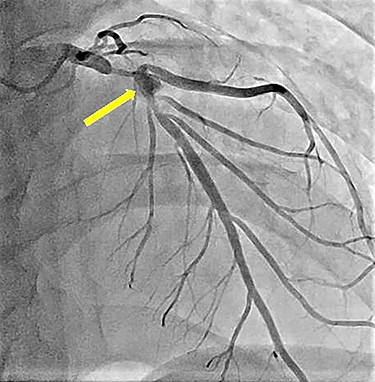

A 20-year-old man with a history of KD was diagnosed with a coronary artery aneurysm in his left anterior descending artery. His condition was controlled by antiplatelet and anticoagulant therapy, and he had no symptoms. However, coronary angiography showed progression of stenosis (Fig. 1), and his resting full-cycle ratio was 0.39; thus, CABG was planned. In addition, he had a history of two surgical procedures for left spontaneous pneumothorax. The first occurrence of the pneumothorax was a year ago, with recurrence within 6 months. The patient was tall and thin. Bullae also existed on his right lung (Fig. 2), which was possibly the cause of the new pneumothorax, because he had repeated pneumothorax in the other lung. Therefore, we planned bullectomy at the same time.

Preoperative left coronary angiography showing the coronary artery aneurysm in the left anterior descending artery (arrow) and severe stenosis at its distal and proximal sides.